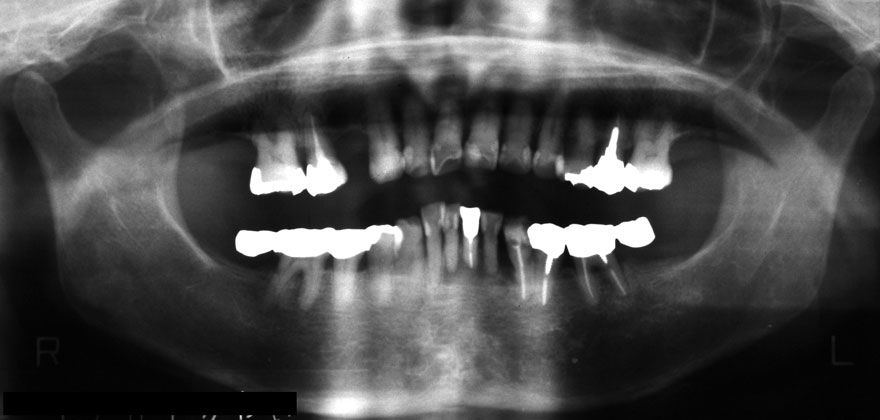

初診時 42歳 男性 平均歯槽骨喪失量:5.30mm

22年後 64歳

平均歯槽骨喪失量:5.554mm

22年間喪失量:-0.24mm

年間喪失速度:-0.01mm

(ケア頻度:1.07ヵ月ごと)